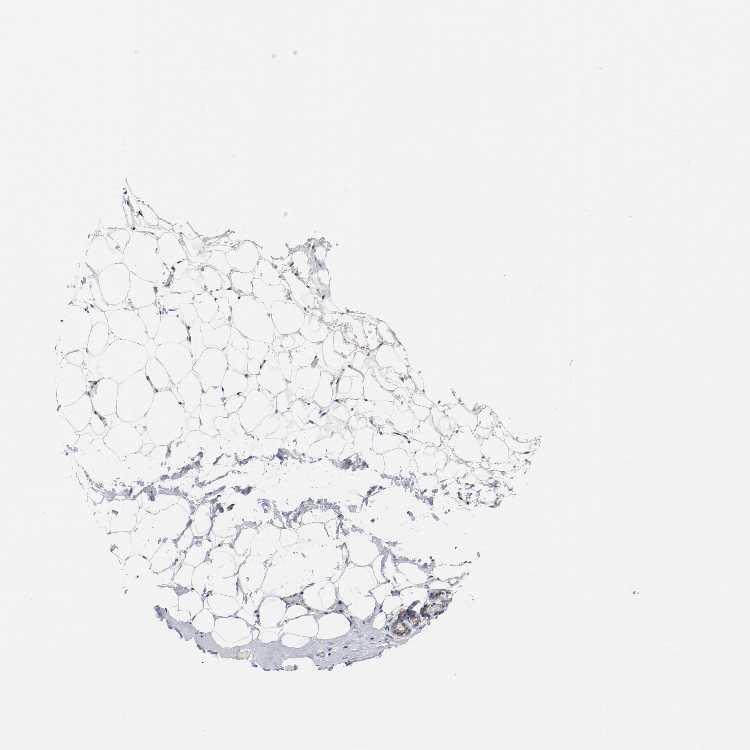

Information about each individual sample is listed below, including gender, age, a tissue section image and estimated fractions of cell types. nTPM (normalized transcripts per million) values give a quantification of the gene abundance which is comparable between different genes and samples.

Female, age 52

Breast sample 373

nTPM: 18.5

Cell types%

Glandular cells:

15

Adipocytes:

5

Other cell types:

80

overview

Female, age 80

Breast sample 390

nTPM: 23.4

Female, age 47

Breast sample 405

nTPM: 37.7

90

Female, age 38

Breast sample 410

nTPM: 117.9

40

55